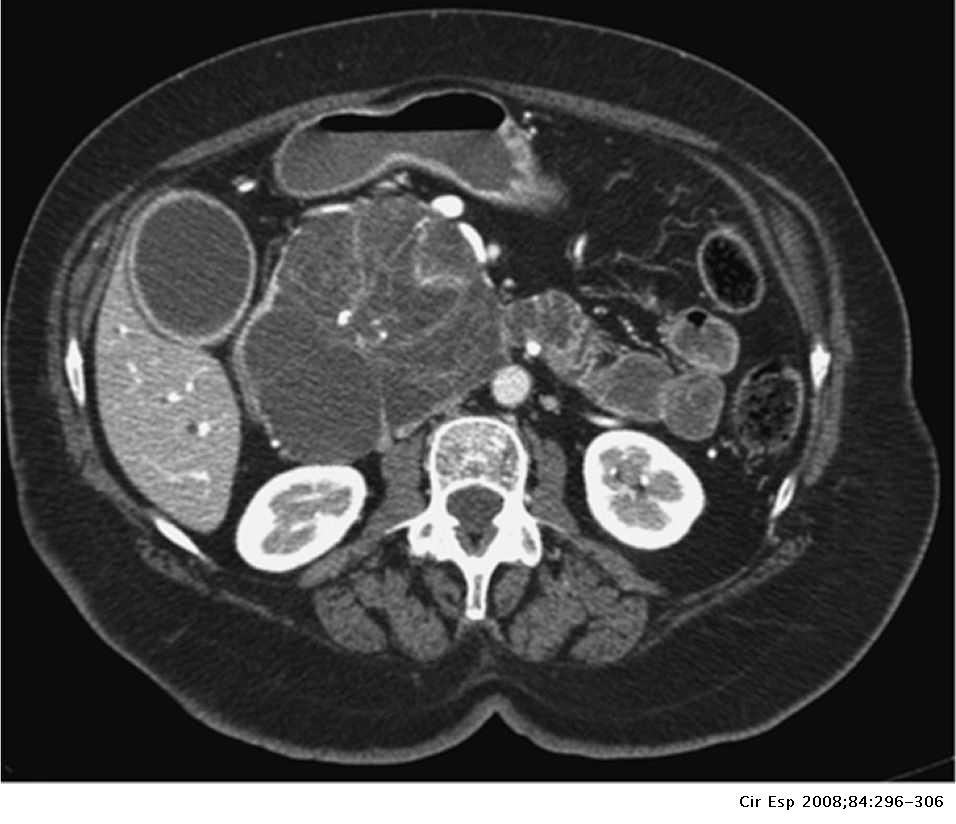

Los patólogos clasifican las neoplasias quísticas serosas en dos grandes grupos. Aquellas que son benignas, que no se han diseminado a otros órganos, se denominan "cistoadenomas serosos".[4] Los cistoadenomas serosos pueden subdividirse en microquístico, oligocístico (o macrocístico), sólido, neoplasia endocrina mixta y neoplasia serosa asociada a VHL. Este último esquema de clasificación es útil porque destaca la variedad de aspectos y las asociaciones clínicas de estas neoplasias. Las neoplasias quísticas serosas que se han diseminado ("metastatizado") a otro órgano se consideran malignas y se denominan "cistoadenocarcinoma seroso".

Estas lesiones rara vez requieren cirugía excepto si son sintomáticas o el diagnóstico está en duda. Dado que no tienen potencial maligno, la observación a largo plazo es innecesaria. La cirugía puede incluir la extirpación de la cabeza del páncreas (una duodenopancreatectomía), la extirpación del cuerpo y la cola del páncreas (una pancreatectomía distal) o, rara vez, la extirpación de todo el páncreas (una pancreatectomía total).[5] En algunos casos, la cirugía se puede realizar utilizando técnicas mínimamente invasivas, como la laparoscopia.[6]